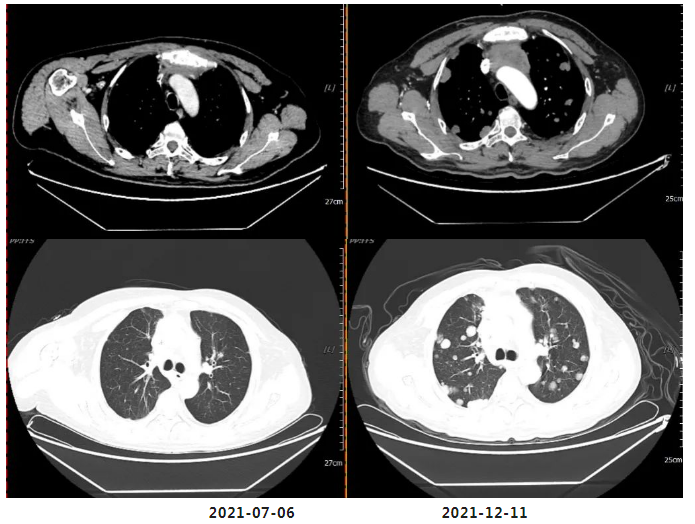

2021年12月11日疗效评价:PD(两肺及胸膜结节明显增多、增大;纵隔前间隙、纵隔内及两肺门转移淋巴结(现约4.7×3.5cm)较前增多、增大,上腔静脉、左头臂静脉受累狭窄;双侧小脑半球、大脑半球转移(约2.1×1.7cm)新发。

2023年1月30日开始口服“马来酸阿法替尼片(自带)40mg 口服 qd”靶向治疗。

2023年3月3日我院复查胸腹盆平扫CT、头颅平扫MR:疗效评估:SD(病情稳定)